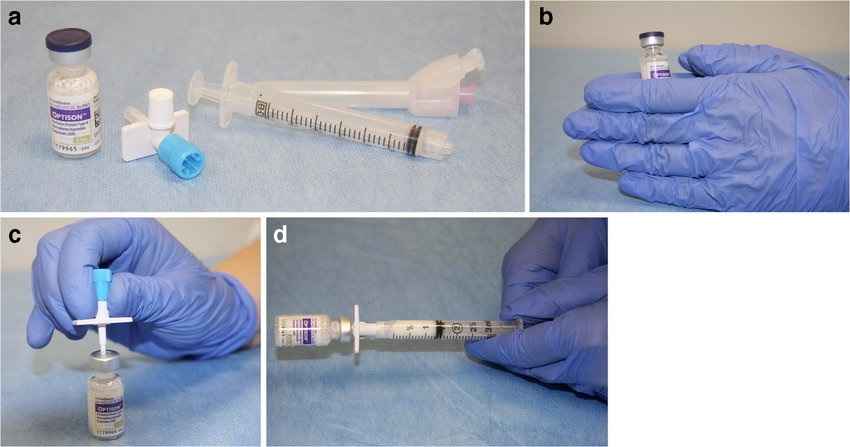

مراحل انجام

- آماده سازی: بیمار مانند اکوی معمولی دراز می کشد و پروب دستگاه روی سینه قرار می گیرد.

- ایجاد خط وریدی (IV): یک رگ کوچک در بازو یا دست بیمار گرفته می شود تا کنتراست تزریق شود.

- تزریق: مقدار بسیار کمی از ماده کنتراست (میکروحبابها) از طریق رگ تزریق می شود.

- تصویر برداری فوری: پزشک بلافاصله پس از تزریق، تصویر برداری را انجام می دهد. کنتراست معمولا تنها برای چند دقیقه در گردش خون باقی می ماند و تصاویر با وضوح بالا در همین زمان کوتاه ثبت می شوند.